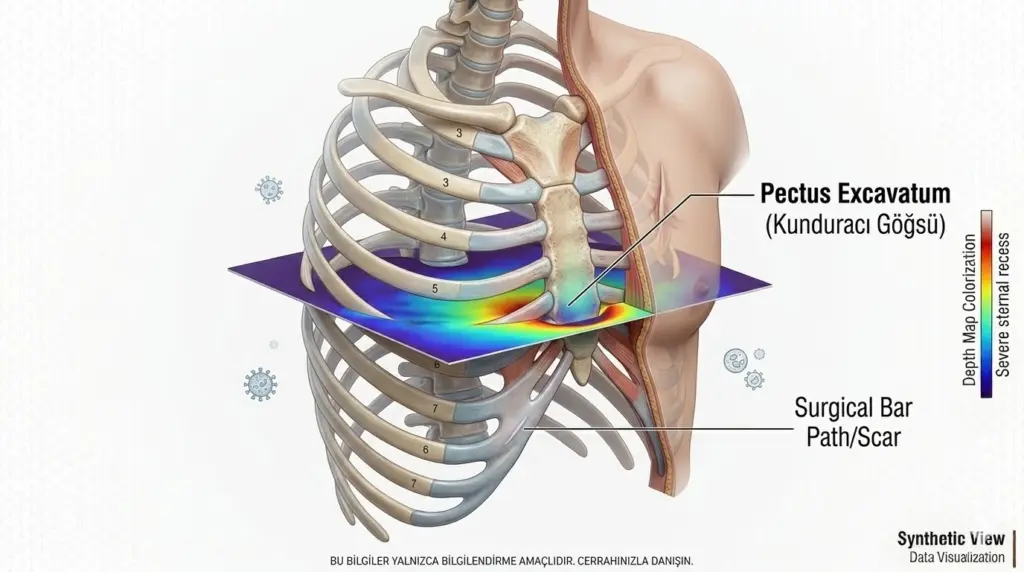

Nuss ameliyatı, kunduracı göğsü (pektus ekskavatum) tedavisinde kullanılan, minimal invaziv (kapalı) bir cerrahi yöntemdir. Geleneksel açık ameliyatlara göre...

Kunduracı göğsü, tıp literatüründeki adıyla Pektus Ekskavatum, iman tahtası olarak bilinen sternum kemiğinin omurgaya doğru çökmesiyle karakterize bir...

Nuss ameliyatı, kunduracı göğsü (pektus ekskavatum) tedavisinde kullanılan, minimal invaziv (kapalı) bir cerrahi yöntemdir. Geleneksel açık ameliyatlara göre çok daha...

Kunduracı göğsü, tıp literatüründeki adıyla Pektus Ekskavatum, iman tahtası olarak bilinen sternum kemiğinin omurgaya doğru çökmesiyle karakterize bir göğüs kafesi...